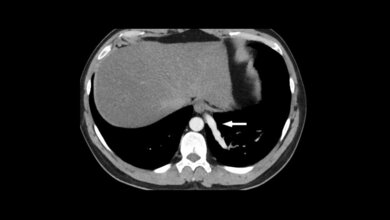

Artefakte können die diagnostische Qualität der Aufnahmen beeinflussen. Auch in der Radiotherapie müssen für eine exakte Therapieplanung die Artefakte reduziert werden. Metallische Implantate können in der Magnetresonanz-Bildgebung erhebliche Artefakte verursachen, insbesondere Signalverluste, Signalverstärkungen, geometrische Verzerrungen und Veränderungen in der Fettsuppression. Die Zusammensetzung des Prothesenmaterials bestimmt das Ausmaß der Artefakte und die Qualität der MR-Aufnahmen.

Artifacts may influence the diagnostic quality of the images. In radiotherapy treatment planning, the reduction of CT artifacts is also very important. Metal implants cause severe artifacts on MRI, especially in signal-loss, signal-pileup, geometric distortion, and failure of fat-suppression. The composition of prosthetic implants is decisive in determing the quality of MR imaging.